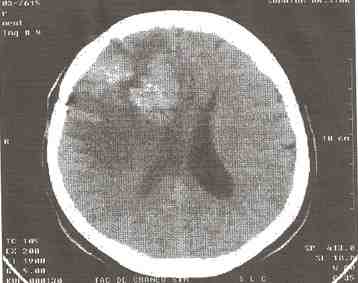

más frecuentes son el glioblastoma multiforme seguido de los astrocitomas de alto y bajo grados, localizados en su mayoría en hemisferios cerebrales y en el cerebelo (25).

En la investigación realizada la caracterización arrojó que predominó el sexo femenino, en los pacientes comprendidos entre las edades de 45-54 años, la sintomatología predominante fue la cefalea, el tumor de más frecuente en aparición fue el glioblastoma multiforme y los hemisferios cerebrales fueron los más afectados según su localización, acompañado del efecto de masa como lesión relacionada con el tumor; y fueron las imágenes hipodensas las que más caracterizaron a los tumores supratentoriales, constatamos que existió una adecuado correlación diagnóstica entre los resultados de la TAC y los anatomopatológicos.